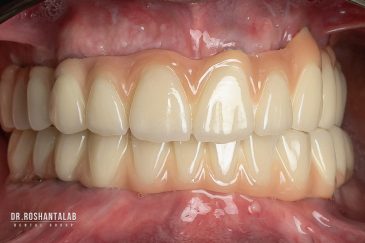

دندانپزشکی زیبایی

طراحی لبخند هالیوودی با متدهای لمینت سرامیکی دندان و کامپوزیت ونیر در کنار اصلاح فرم، خدمات بلیچینگ و روکش دندان، زیبایی چهره شما را تکمیل میکند.ترمیم دندان

برای اصلاح طرح لبخند بدون جلب توجه، از جدیدترین تکنولوژی الاینر و ارتودنسی شفاف استفاده کنید. ما تخصصیترین خدمات ارتودنسی دندان را با قیمت مناسب و شرایط اقساط ویژه ارائه میدهیم.کاشت دندان توسط بهترین متخصص ایمپلنت